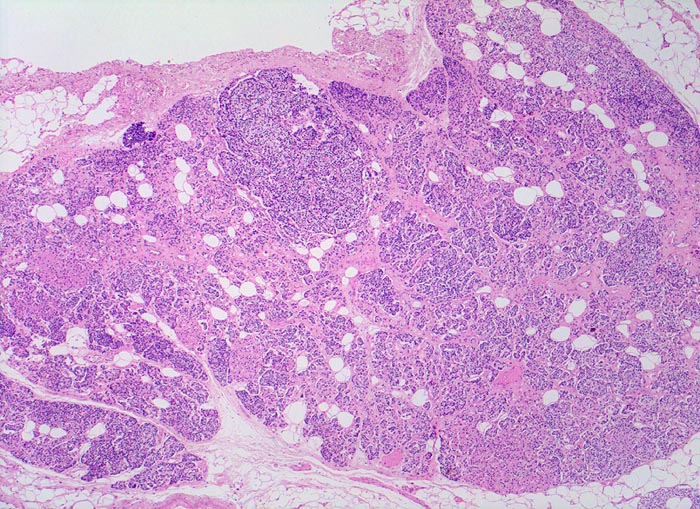

Morphologisch besteht bei sHPT eine Hauptzellhyperplasie. Makroskopisch findet sich eine meist ungleich ausgebildete Vergrösserung aller Nebenschilddrüsen. Die Grösse der Drüsen entspricht der Schwere und der Dauer des Stimulus. Die im früheren Stadium gefundene diffuse Hyperplasie mit Ersatz des Stromas und der Fettzellen durch chronisch stimulierte Hauptzellen (> 558) (> 559) geht im späteren Stadium in eine noduläre Hyperplasie („Pseudoadenome“) über (> 2358). Die regulierte Anpassung der Nebenschilddrüsen kann in eine Autonomie übergehen (tHPT) (> 3704). Morphologisch besteht in diesem Fall eine unregelmässige noduläre Hyperplasie. Gelegentlich entwickelt sich beim tHPT ein dominanter Knoten, der morphologisch nicht von einem Adenom bei pHPT unterscheidbar ist.

• Knotige vergrösserte Nebenschilddrüse. Abgrenzung der einzelnen Knoten durch breite Fibrosebänder.

• Hyperplasie lipidarmer Hauptzellen.

• Verminderter Fettgehalt (<<35%). Für normale Nebenschilddrüsen gilt: